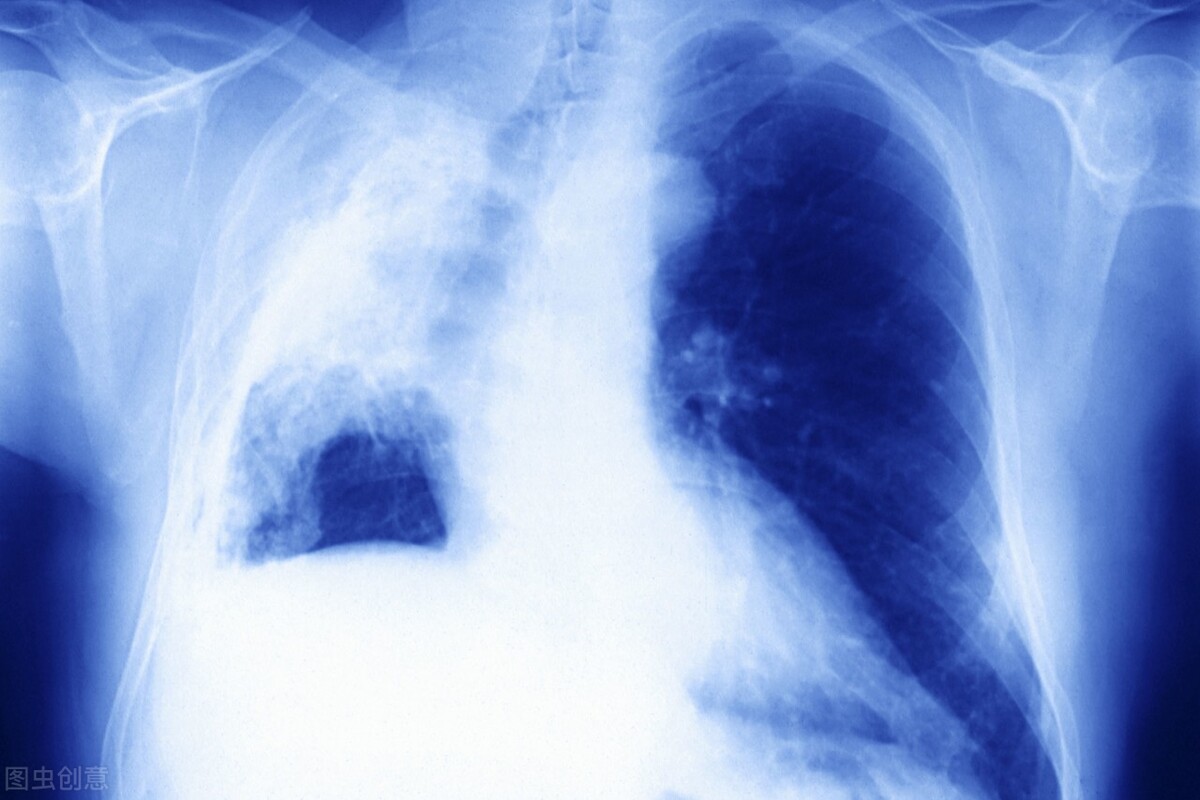

不治疗并不是明智之举,肺癌细胞在生长过程中会破坏血管、侵犯神经,一部分病人会因大咯血而窒息,一部分病人会因大量胸水出现呼吸衰竭,还有一些病人会出现剧烈疼痛,吃不下,睡不着。总之,临终前,他们会经历各种各样的折磨,最后痛苦地死去。

从更大的角度来看,肺癌分为小细胞肺癌和非小细胞肺癌,而在小细胞肺癌的治疗中,过去没有很好的治疗方法,但近年来迎来了首次重大突破。

PD-L1*制剂抑**阿替利珠单抗联合化疗可以大大改善小细胞肺癌患者的整体生存期,目前美国FDA已经批准化疗联合阿替利珠单抗作为小细胞肺癌的一线标准治疗方案。